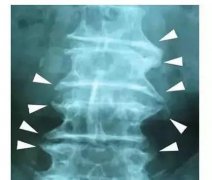

QZ16030094 姓名:陈先生 性别:男 年龄:32岁

- 病情

AS ①晚期 ②重度 病史:5年+

- 治疗

治疗后骶髂关节疼痛消失,腰椎前屈、背伸侧弯活动自如,膝关节无压痛感,复查血沉、C反应蛋白、等各项检查均已达到临床康复的标准。